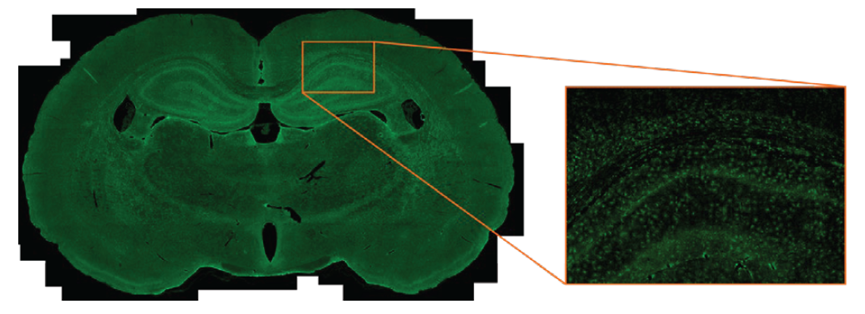

線性模式采集,實現定量分析

Evident提供了滿足不同應用需求的多款顯微數碼相機。在選擇您需要的相機時,合適的參數至關重要;我們不同型號的顯微相機可涵蓋從一般生物學研究、教學、病理研究、細胞培養、胚胎學和藥物研發等的多種應用場景。Evident的DP顯微相機家族產品適用于包括熒光、明場和紅外成像在內的多種觀察方法。

Evident了解成像對于您的重要性,我們的顯微數碼相機以優良的光學器件、出色的細節和智能成像功能幫助您觀察圖像細節并提高工作質量。